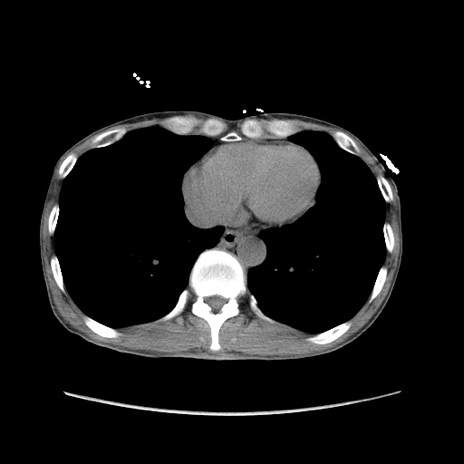

症例11(横断像)

【症例】 60歳代男性

【主訴】 下腹部痛

【現病歴】 本日夜中より下腹部痛の症状認め、受診。

【既往歴】 膀胱癌(膀胱全摘+尿管皮膚瘻術) 、胃癌術後

【身体所見】 BT 35.3℃、PR 58/min、BP 136/98mHg、腹部平坦、軟、腸蠕動音±、ストマ留置あり、左上腹部~正中部に圧痛あり、反跳痛なし。

【データ】WBC 5100、CRP0.01